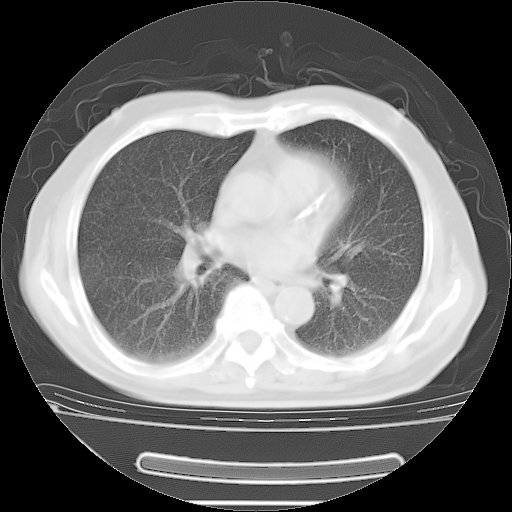

今天复查肺部CT,发现双肺广泛磨玻璃样改变。所以我把3月19日和5月9日相隔50天的肺部CT上传。请大家会诊。

5月9日肺部CT(在4月27日齐鲁医院肺部CT描述部分肺组织磨玻璃样改变,12天后肺组织广泛磨玻璃样改变)

大致读了系列胸部CT:纵隔窗无明显异常,肺窗:从4、27至今:主要是双肺中下野外带可见毛玻璃样改变,目前处于急性肺泡炎阶段,至于原因考虑1、结替组织或胶原血管性疾病所致?2、恶性疾病如恶组在肺部所致的表现或细支气管肺泡癌?3、药物或其它原因如肺蛋白沉着症所致肺泡炎目前不太可能?总之,明天就去请我院的呼吸科、感染科、血液科和临免专家会诊哈。